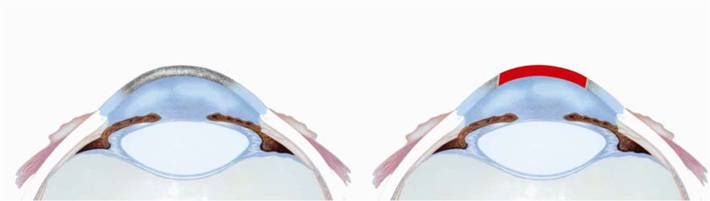

Рис. 1.2.1. Схема сквозной оптической кератопластики: а) до операции; б) после операции, трансплантат красный

а

Рис. 1.2.3. Схема послойной задней кератопластики: а) до операции; б) после операции, трансплантат красный

Рис. 1.2.7. Схема секторальной покровной кератопластики: а) до операции; б) после операции, трансплантат красный.

Рис.

1.2.9. Схема межслойной кератопластики: а) до операции; б) после операции, трансплантат красный